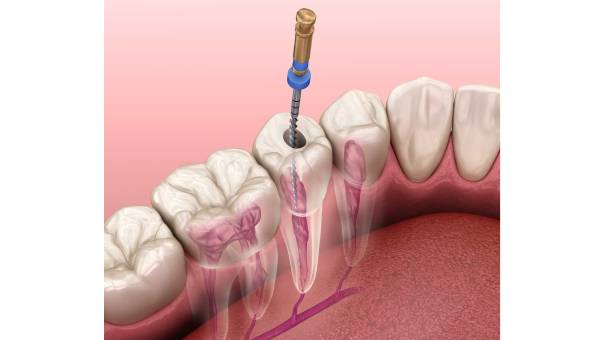

Root canal treatment (RCT) is one of the most effective dental procedures for saving a natural tooth that has been damaged by infection or decay. Many people associate root canals with pain, but modern dental techniques and anesthetics, when done properly, have made the process painless, comfortable, quick, and highly successful.

A standard RCT involves the following stages: